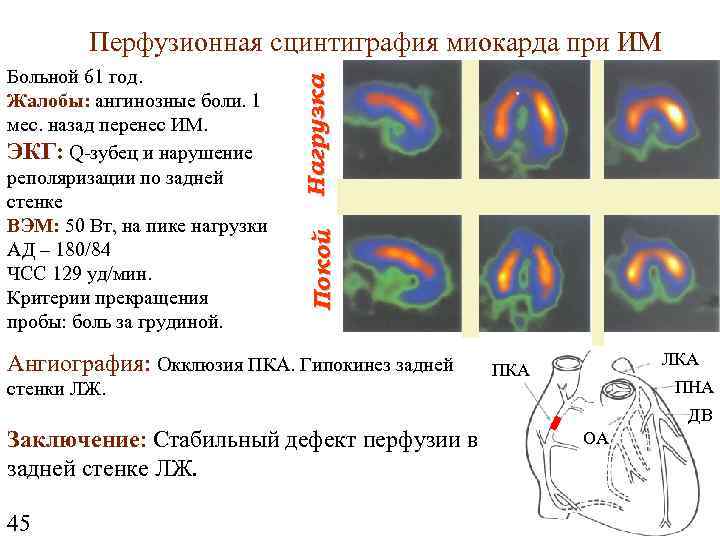

Покой Больной 61 год. Жалобы: ангинозные боли. 1 мес. назад перенес ИМ. ЭКГ: Q-зубец и нарушение реполяризации по задней стенке ВЭМ: 50 Вт, на пике нагрузки АД – 180/84 ЧСС 129 уд/мин. Критерии прекращения пробы: боль за грудиной. Нагрузка Перфузионная сцинтиграфия миокарда при ИМ Ангиография: Окклюзия ПКА. Гипокинез задней стенки ЛЖ. ЛКА ПНА ДВ Заключение: Стабильный дефект перфузии в задней стенке ЛЖ. 45 ОА

Покой Больной 61 год. Жалобы: ангинозные боли. 1 мес. назад перенес ИМ. ЭКГ: Q-зубец и нарушение реполяризации по задней стенке ВЭМ: 50 Вт, на пике нагрузки АД – 180/84 ЧСС 129 уд/мин. Критерии прекращения пробы: боль за грудиной. Нагрузка Перфузионная сцинтиграфия миокарда при ИМ Ангиография: Окклюзия ПКА. Гипокинез задней стенки ЛЖ. ЛКА ПНА ДВ Заключение: Стабильный дефект перфузии в задней стенке ЛЖ. 45 ОА